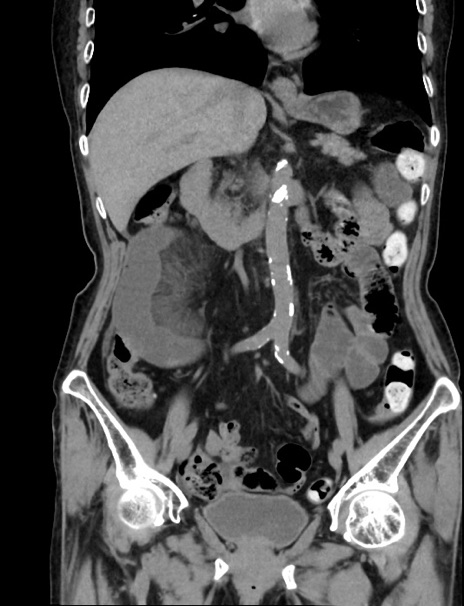

症例33(冠状断像)

【症例】70歳代 女性

【主訴】心窩部痛

【現病歴】延髄病変の精査・加療にて神経内科入院中。本日より心窩部痛あり。

【既往歴】虫垂炎

【身体所見】右下腹部を中心に圧痛と反跳痛あり。

【データ】WBC 10900、CRP 0.02